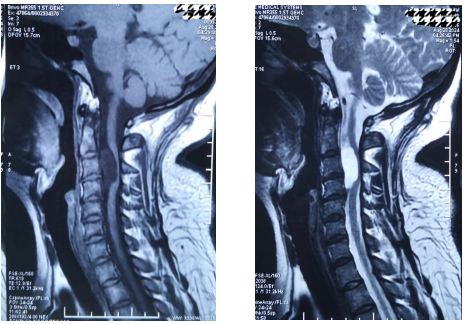

颈椎核磁矢状位显示颈3-4水平椎管内脊髓外囊性病变,位于脊髓腹侧,呈长T1长T2信号,脊髓明显受压变扁

为进一步诊治,杭女士辗转前来北京市垂杨柳医院神经外科寻求帮助。神经外科主任张锟带领全科医生就杭女士的病情展开讨论,认为患者慢性病程,逐渐加重,表现为颈神经根痛症状。颈椎核磁显示颈3-4水平椎管内脊髓外囊性病变,位于脊髓腹侧面,边界清楚,呈长T1长T2信号,脊髓明显受压变扁,打药后无强化。诊断考虑为良性囊性病变,肠源性囊肿可能性最大,为一种少见的先天性病变。手术指征明确,手术难点及风险在于,病变位于高颈髓水平且位于脊髓腹侧面,从后方入路显露病变时需牵拉脊髓及神经根,术后可能出现高位截瘫及呼吸困难。此外囊肿壁可能与脊髓黏连紧密,无法全切病变而导致复发。